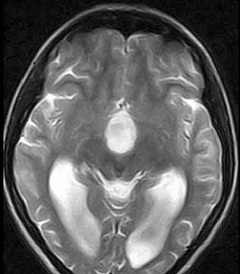

Для диагностики арахноидальной ликворной кисты (кисты, заполненной ликвором) применяют различные методы. Основными среди них являются магнитно-резонансная томография и компьютерная томография для выявления кистозного образования, определения его локализации, размеров. Внутривенное введение контраста позволяет дифференцировать арахноидальную ликворную кисту от опухоли (опухоль накапливает контраст, киста нет).